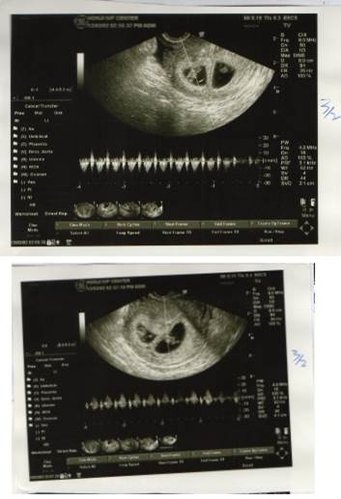

在宏孕诊所第一次我只取到二颗卵,置放5天,一颗为囊胚A级,一颗为B级,玻璃冷冻后,进行第二次疗程,这次取到3颗卵,2颗空包蛋,另1颗的品质似乎不如上次的2颗,因此,我决定植入上次的2颗,很顺利的2颗胚胎都顺利著床,也都有心跳。不过,我想此次成功原因也或许是因为我刺激的卵数少,卵子们能有较多的养分、品质较好有关,不过我想这就交给专家们去研究了!